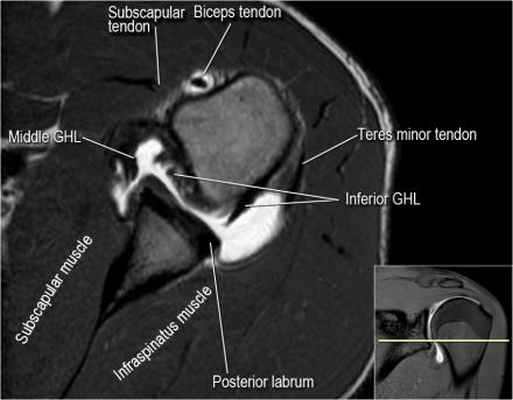

Изображение задних отделов плечевого сустава.

Отображены надостная, подостная и малая круглая мышцы и их сухожилия. Все они прикрепляются к большому бугорку плечевой кости. Сухожилия и мышцы манжеты вращателей участвуют в стабилизации плечевого сустава во время движения. Без манжеты вращателей головка плечевой кости частично сместилась бы из суставной впадины, уменьшив силу отведения дельтовидной мышцы (мышцы вращательной манжеты координирует усилия дельтовидной мышцы). Повреждение манжеты вращателей может привести к смещению головки плечевой кости кверху, в результате вызвая высокое стояние головки плечевой кости.

Нормальная анатомия плечевого сустава в аксиальных изображениях и контрольный список.

- обратите внимание на волокна нижней плече-лопаточной связки. На данном уровне так же ищется повреждение Банкарта.

- изучите область прикрепления нижней плече-лопаточной связки. Изучите нижний комплекс суставной губы и связок. Поищите HAGL-повреждение (humeral avulsion of the glenohumeral ligament).